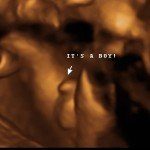

Baby Boutique and gender reveal party supplier.

Our baby boutique offers many unique items to announce the gender of your little one. We offer confetti cannons, powder cannons, flutterfetti sticks, and smoke bombs. We also have a variety of infant outfits and blankets. Our boutique features ultrasound photo frames and unique frames and gifts for grandparents. Record your baby’s heartbeat in one of our adorable animals for a keepsake you will cherish forever.

4D/5D/HD Ultrasound Gallery

Gallery